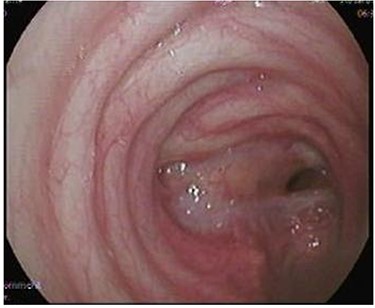

Case 1—bronchial injury

A 27-year-old male presented to the Trauma Room after a fall from a 3-meter height. Because of low Glasgow coma scale (GCS), hypoxia and diffuse subcutaneous emphysema, the patient was intubated, and bilateral chest tubes were inserted. After stabilization, a pan computed tomography (CT) scan was performed and revealed extensive subcutaneous emphysema of the neck and chest, as well as bilateral pulmonary contusion. The patient was admitted to the Trauma intensive care unit (ICU) for supportive treatment, where he continued to have hypoxia as well as a persistent right-sided pneumothorax on a repeated chest X-ray. Because a major airway injury was suspected, a bronchoscopy was performed, which revealed a full-thickness laceration in the region of the bronchus intermedius/right middle lobe bronchus. Due to persistent hypoxia, the ECMO team was consulted and the patient was started on Veno-Venous (VV) ECMO. With ECMO support, he was shifted to the operating theater (OT) for right anterolateral thoracotomy and repair of the bronchial defect. The surgery was uneventful, and the patient returned to the ICU in stable condition. He remained sedated, on lung-protective ventilation, as well as ECMO support. The patient underwent tracheostomy on Day 5 and was successfully removed from ECMO and decannulated on Day 16. He remained in the ICU for 25 days, after which he was transferred to the ward in stable condition. Follow-up flexible bronchoscopy showed an intact bronchial tree, with only a partial occlusion of the lumen. The patient was discharged home in stable condition with regular follow-up in the outpatient clinic.